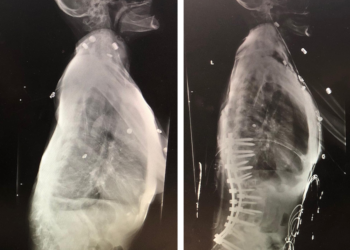

Spine:

Thoracic Spinal Cord Tumor Case Presentation

Author: Xavier P. J. Gaudin D.O., F.A.C.O.S., Read More!